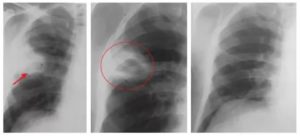

Выполнив рентгеновский снимок в различных проекциях, выявить на нём наличие абсцесса легких можно по присутствию таких факторов:

- выделение признаков, характерных для наличия круглой тени;

- присутствуют нечёткие границы (может свидетельствовать о том, что заболевание сопровождается воспалительным процессом);

- интенсивность средней степени;

- выделяется однородность содержимого (указывает на наличие гнойника);

- рядом с пораженной стороной наблюдается увеличение размеров лимфатических узлов в корне;

- имеется полость распада, которая размещена в средней области просветления;

- утолщенные стенки, при этом внутри они не являются равномерными;

- повышенный или пониженный уровень жидкости во внутренней зоне кольца.

Рентгенограмма абсцесса лёгкого на различных стадиях развития болезни может показать абсолютно разные картины.

На ранних стадиях развития болезни на снимке присутствуют следующие проявления:

- Во время первичных стадий абсцесса пораженная зона небольшая, от 1 до 4 см.

- Вокруг кольцевидной тени размещены очаги воспаления перифокального типа.

- Происходит деформирование легочного рисунка.

- Присутствует тенденция к возрастанию уровня жидкости.

По истечении некоторого времени внутренняя часть стенки кольцевидной тени подвергается уплотнению, и в результате этого исчезают её шероховатости.

Когда абсцесс находится в процессе прорыва гнойника в области бронхов, на снимке с рентгена можно увидеть следующие изменения:

- стенки полости становятся гораздо тоньше;

- в центре пораженной зоны присутствует просветление, где имеется горизонтальный уровень жидкости;

- выше имеющегося уровня жидкости присутствуют области с некрозом тканей;

- по причине воспаления по гнойному типу внешняя сторона капсулы становится не такой четкой.

А вот для определения очистившейся формы легочного абсцесса следует обратить внимание на следующие моменты:

- стенки капсулы становятся намного тоньше;

- отсутствует уровень жидкости;

- происходит зарастание стенок полости с помощью соединительной ткани, это способствует тому, что очистившийся абсцесс ещё какое-то время остаётся в первичном размере, а затем заменяется рубцом.

Рентгенологические признаки в стадии распада (прорыва абсцесса в бронхи) отличаются более выраженной картиной, позволяющей определить полость с уровнем жидкости, увидеть газ, расположенный над жидкостью в виде осветленного полукруга.

Для выявления размеров и расположения полостей снимки рекомендуется делать в нескольких стадиях наполнения плевральной полости жидкостью, например, до и после отхаркивания и в нескольких проекциях. Полость абсцесса на рентгенологических снимках чаще всего имеет овальную форму.